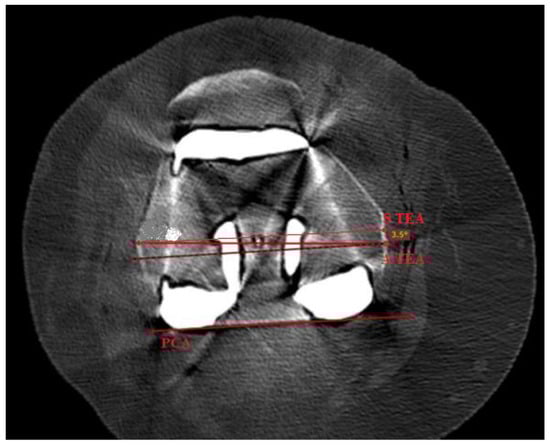

All patients underwent a CT scan at 6 weeks follow up appointments with use of a multislice scanner (General Electric Light Speed Plus; GE Medical System, Milwaukee, WI, USA) to determine the rotational alignment of the components. The CT scan sequence was between 10 cm proximal to the superior pole of the patella and 10 cm distal to the tibial tuberosity and was made in contiguous 2.5-mm slices. Specifically, we measured the anatomic rotational axis on postoperative CT scans in knees of patients undergoing conventional primary TKA (mTKA). We then measured the femoral component rotational alignment optimized by a robotic system (raTKA), which took into account constitutional anatomy of the patient and best functional performance to the posterior condylar axis (PCA) and measured the difference between the femoral component rotation and the actual transepicondylar axis (TEA) (Figure 3).

Figure 3.

Postoperative TKA CT scan of one of the patients analyzed in the study. It reveals the graphical representation of S TEA and PCA lines, utilized and described in the study methods.

Femoral rotation in the following study was defined based on the postoperative CT scans as the angle subtended by a line between the most prominent parts on lateral and medial sites (A TEA) and the line between most posterior parts of the condylar components on the medial and lateral sides of the femur, the so called PCA (Figure 3), according to the Berger protocol [24]. After recognition of both lines of the interest, namely the A TEA and PCA, the line parallel to PCA was subtended upward to reach a common point with A TEA. The angle created by both of the lines was recorded as the femoral component rotational alignment. Internal rotation relative to the PCA was given a negative value and external rotation was given a positive value. All radiographic and CT parameters were measured three times (with a 3-day interval between measurements). Two doctors (A.S. and K.M.) performed these measurements on the CT scans of all knees. An experienced arthroplasty surgeon (P.C) measured 20 randomly selected knee CT scans. A fellowship-trained arthroplasty surgeon (J.S.) also measured 20 randomly selected knee CT scans for the calculation of interobserver agreement and correlation. Intraobserver agreement ranged from 0.94 to 0.97.

Our study is in agreement with aforementioned papers and demonstrates statistically significant adequacy in radiographically measured femoral component rotational alignment in the NAVIO and CORI groups. The robotic navigation enables a personalized approach with both NAVIO and CORI and balance the knee within the ligamentous tension. We believe that a modern orthopaedic surgery should consider ligamentous tension. Thus, bone references may be the first step to more reliable and reproducible implant positioning to recreate the joint functioning among different arthritic deformities correction. There are several possible methods for detection of rotational alignment, while in this study we utilized one: surgeon uses bone landmarks of the femur intraoperatively as a reference is shown in Figure 3: transepicondylar axis (TEA): Anatomical (lateral to medial epicondyle) or surgical (medial sulcus lateral epicondyle) axis, which has low reproducibility and reliability levels; posterior condylar line (a very reliable reference); Trochlear AP axis, which is known as the Whiteside line.

Intraoperatively, the right determination of epicondyles is not always possible. If the reference on lateral condyle is unique on the apex of bony prominence, there are two possible references for the medial condyle: The apex of the medial prominence defines the anatomical TEA (A TEA); and the surgical TEA (S TEA) connects the lateral condyle and the medial sulcus on the femur. The chose A TEA, which was made according to Robertson et al. conclusions, that is, the measurements using the A TEA transepicondylar axis are easier to replicate compared to the S TEA axis [34].